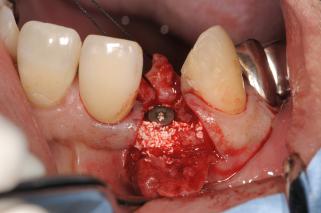

頬側の裂開に対して、Bio-ossとCGFメンブレンでGBRをしています。